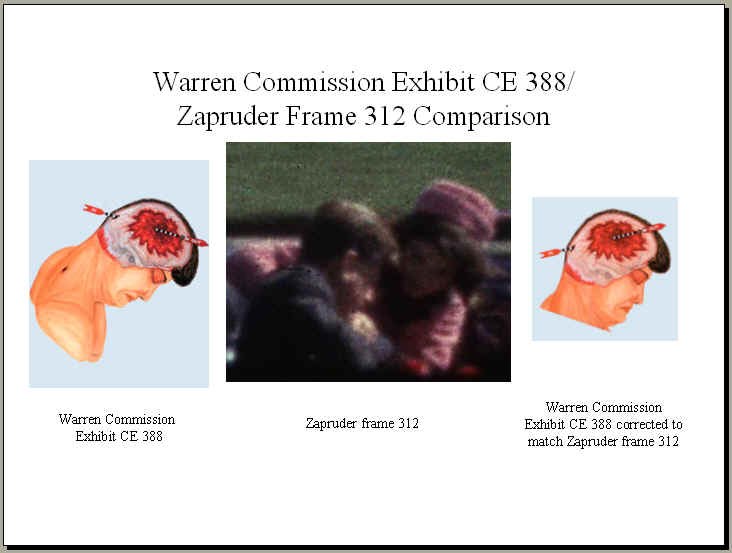

That's what "photo experts" like Robert Groden (in The Killing of a President, page 81) and Harrison Livingstone (in High Treason II) do. Wanting to show the back of Kennedy's head blown out — and thus push the notion of a Grassy Knoll shooter — they use a close-up autopsy photo of the inside of Kennedy's skull after the brain was removed. By rotating the photo ninety degrees clockwise, they can make it appear that the photo shows a large defect in the back of Kennedy's head. In actuality, Kennedy was photographed from the front, and the photo shows the top if his head blasted out, as shown in this drawing by Dr.

Robert Artwohl. Finally, a large and properly-oriented copy of the head photo.

http://mcadams.posc.mu.edu/experts.htm#rotateMcAdams selbst liefert keine Belege für die angeblich falsche ausrichtung- er dreht es nur und sagt, dass sei die richtige. Als unabhängigen Beleg fürht er die Arbeit Artwohls an